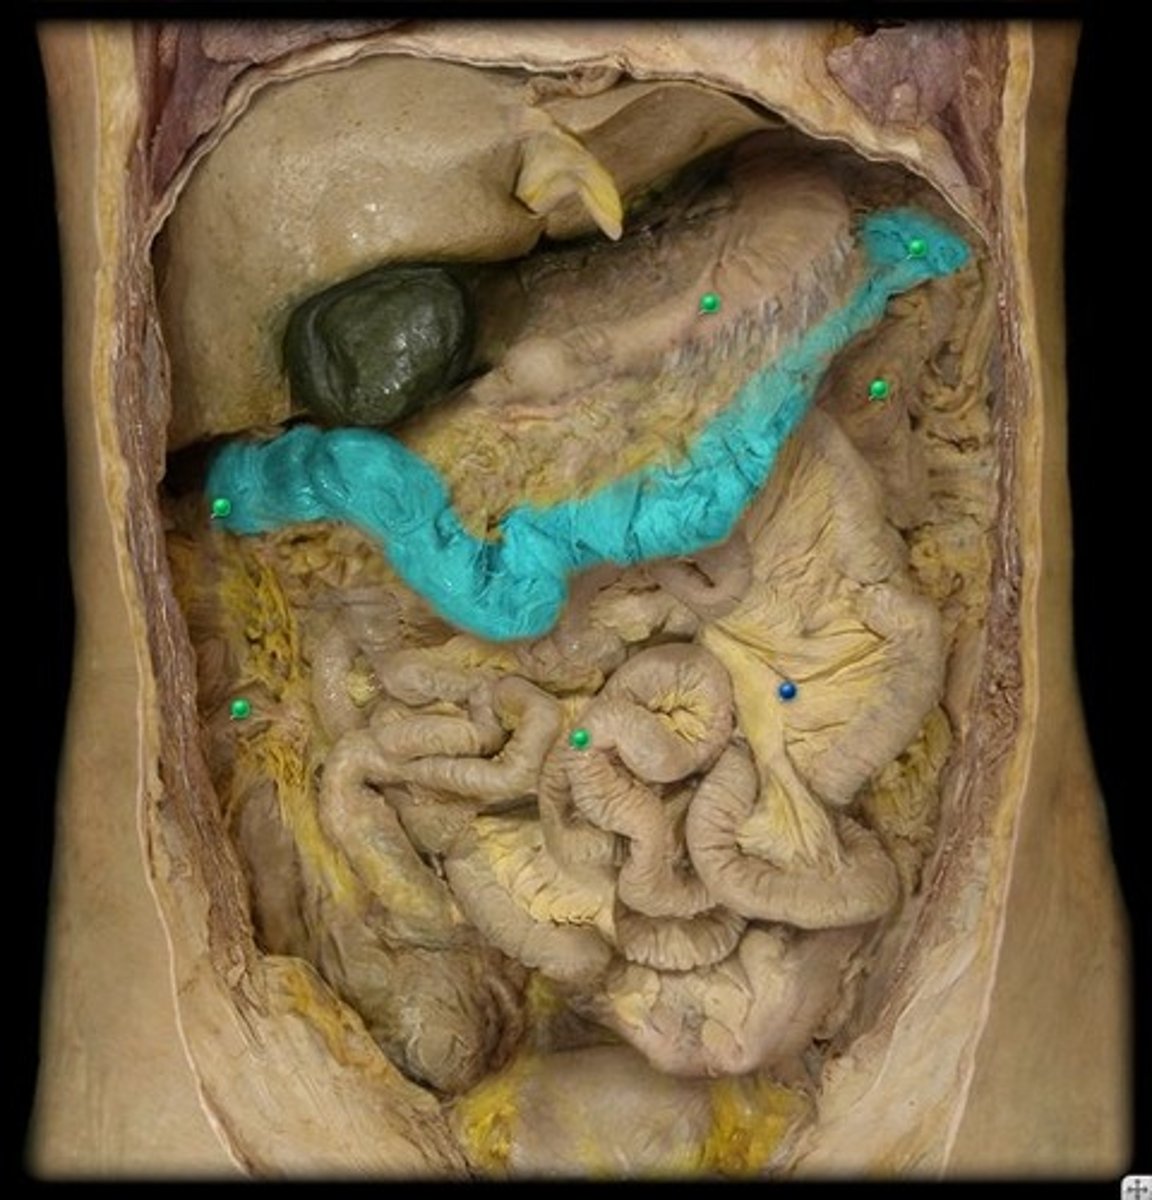

GI anatomy pin test

128 Terms

duodenum

head (of pancreas)

body (of pancreas)

tail (of pancreas)

main pancreatic duct

accessory pancreatic duct

hepatopancreatic ampulla

pancreatic + bile duct

pancreas

gallbladder

fundus (gallbladder)

body (gallbladder)

neck (gallbladder)

duodenojejunal junction

jejunum